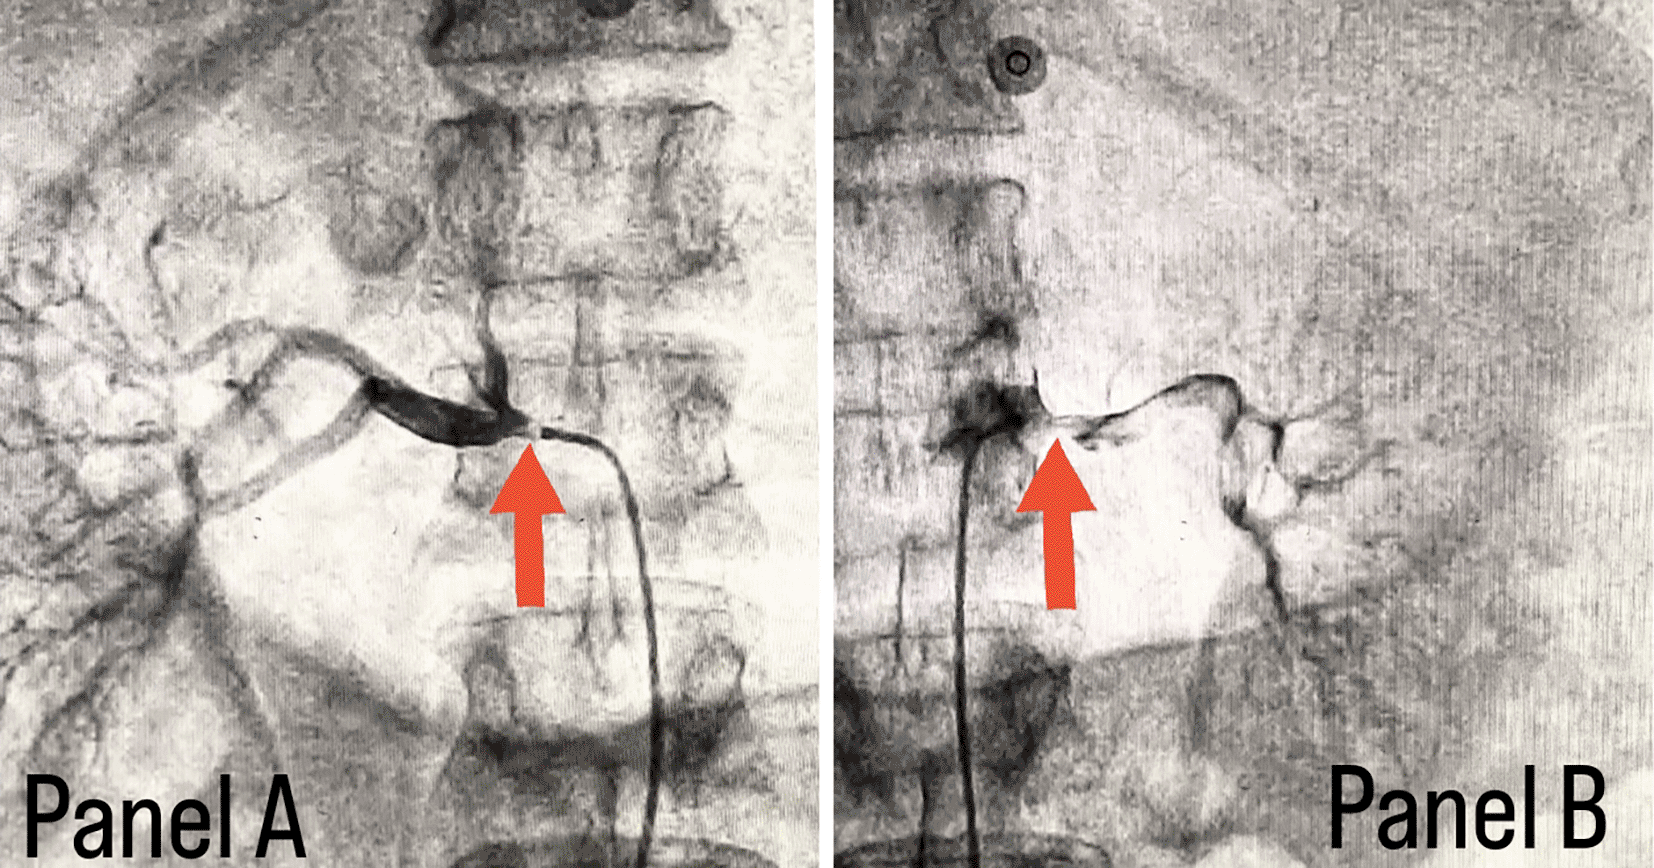

Coronary angiography was done and a triple vessel coronary artery disease was diagnosed as shown in Figure 1; in which, panel A shows stenosis in proximal Left circumflex artery (LCX) with a black arrow, panel B shows a stenotic lesion in proximal Left anterior descending artery (LAD) with a black arrow and panel C shows 100% stenosed Right coronary artery (RCA) with a black arrow. A subclavian puncture was taken to look for a subclavian artery considering the claudication symptoms of the patient and peripheral vascular disease was diagnosed with bilateral subclavian artery stenosis as shown in Figure 2, in which panel A shows right subclavian artery stenosis and panel B shows left subclavian artery stenosis marked with yellow arrows. Considering the severity of claudication pain in our case, bilateral renal and femoral arteries were also checked via aortic flush and bilateral renal artery ostial stenosis was seen. Figure 3 panel A shows right renal ostial stenosis and panel B shows left renal ostial stenosis marked with red arrows.